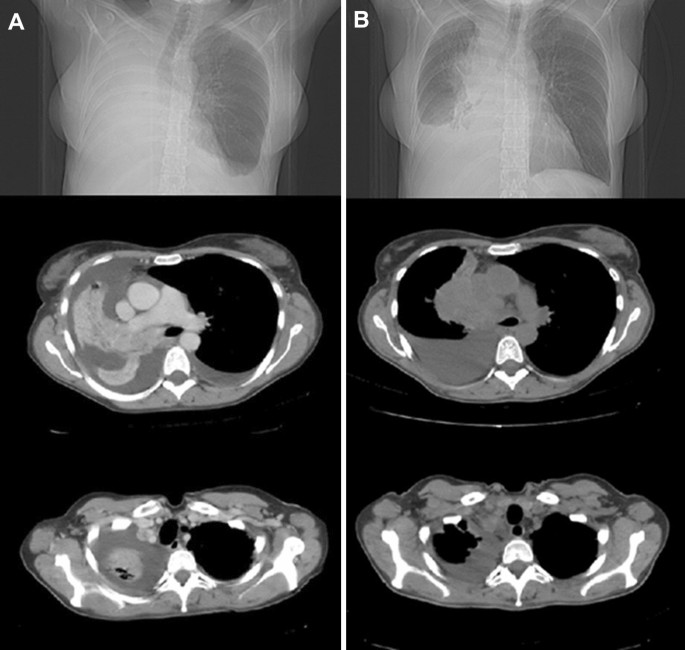

Figure 2 shows the radiological response of an advanced non-small cell lung tumor after palliative RT. A complete or partial symptomatic response was recorded in 51 (28.3%) and 109 (60.5%) patients, respectively, with 88.8% (95% CI 83.3–92.7%) overall response rate and four months median time to symptoms progression. The pre- and post-treatment mean VAS was 5.3 (± 7.7) and 2.2 (± 2.2) respectively (p < 0.00001). At first follow-up, 76 (42.2%), 84 (46.7%), and 20 (11.1%) patients showed improved, stable, and worse ECOG performance status, respectively. An improvement of CLAS 1, 2, and 3 scores was recorded in 80 (48.2%), 70 (42.2%), and 77 (46.4%) out of 167 evaluable patients, respectively. Four patients (2.2%) presented Grade ≥ 3 acute toxicity while one patient (0.6%) showed Grade 3 late toxicity. Comparing the symptomatic effect of the SHARON regimen between anatomical sites, histological types, ECOG scores and RT doses (< 18 vs ≥ 18 Gy) no significant differences were recorded (data not shown). Similarly, the response rate of the different symptoms was similar, without significant differences (data not shown). In contrast, patients with locally advanced disease showed a higher rate of symptomatic responses than metastatic ones (97.3% vs 83.0%; p = 0.021). Finally, the complete pain response rate was more than double in patients with mild to moderate (VAS: 4–7) pain compared to those with severe (VAS > 7) pain (36.0% vs 14.3%; p = 0.028).